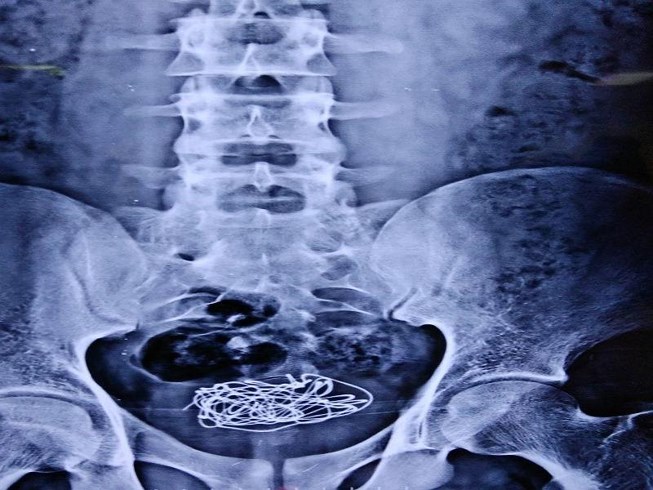

03/10/2018 22:41Nhét dây điện vào 'của quý', lọt đến tận bàng quang

Bệnh nhân người Anh này nhập viện do bị đau nhiều ở bụng dưới, rát khi tiểu. Theo lời kể của cậu ta, 10 ngày trước cậu đã nhét một sợi dây điện vào niệu đạo, đây là ống trong dương vật thông với bàng quang, có nhiệm vụ lưu thông nước tiểu cùng tinh dịch. Đáng lo ngại là đây không phải lần đầu tiên cậu thực hiện việc này.

Mặc dù các bác sĩ đã cố gắng lấy sợi dây điện thông qua phẫu thuật nội soi bàng quang, nhưng sợi dây bị rối và quấn quanh bàng quang đến mức không thể di chuyển nó. Cuối cùng, bác sĩ phải sử dụng tia laser để cắt nhỏ sợi dây thành nhiều đoạn, sau đó gây mê cục bộ phẫu thuật lấy các mảnh dây này ra, đồng thời chèn vào bàng quang 1 vỏ bọc.

Theo các bác sĩ, việc phải phẫu thuật các vật thể lạ trong bàng quang và niệu đạo xảy ra khá thường xuyên. Các vật này bao gồm từ dây sạc điện thoại, pin tiểu đến đầu bút, cọng cỏ, thậm chí là cá nhỏ…